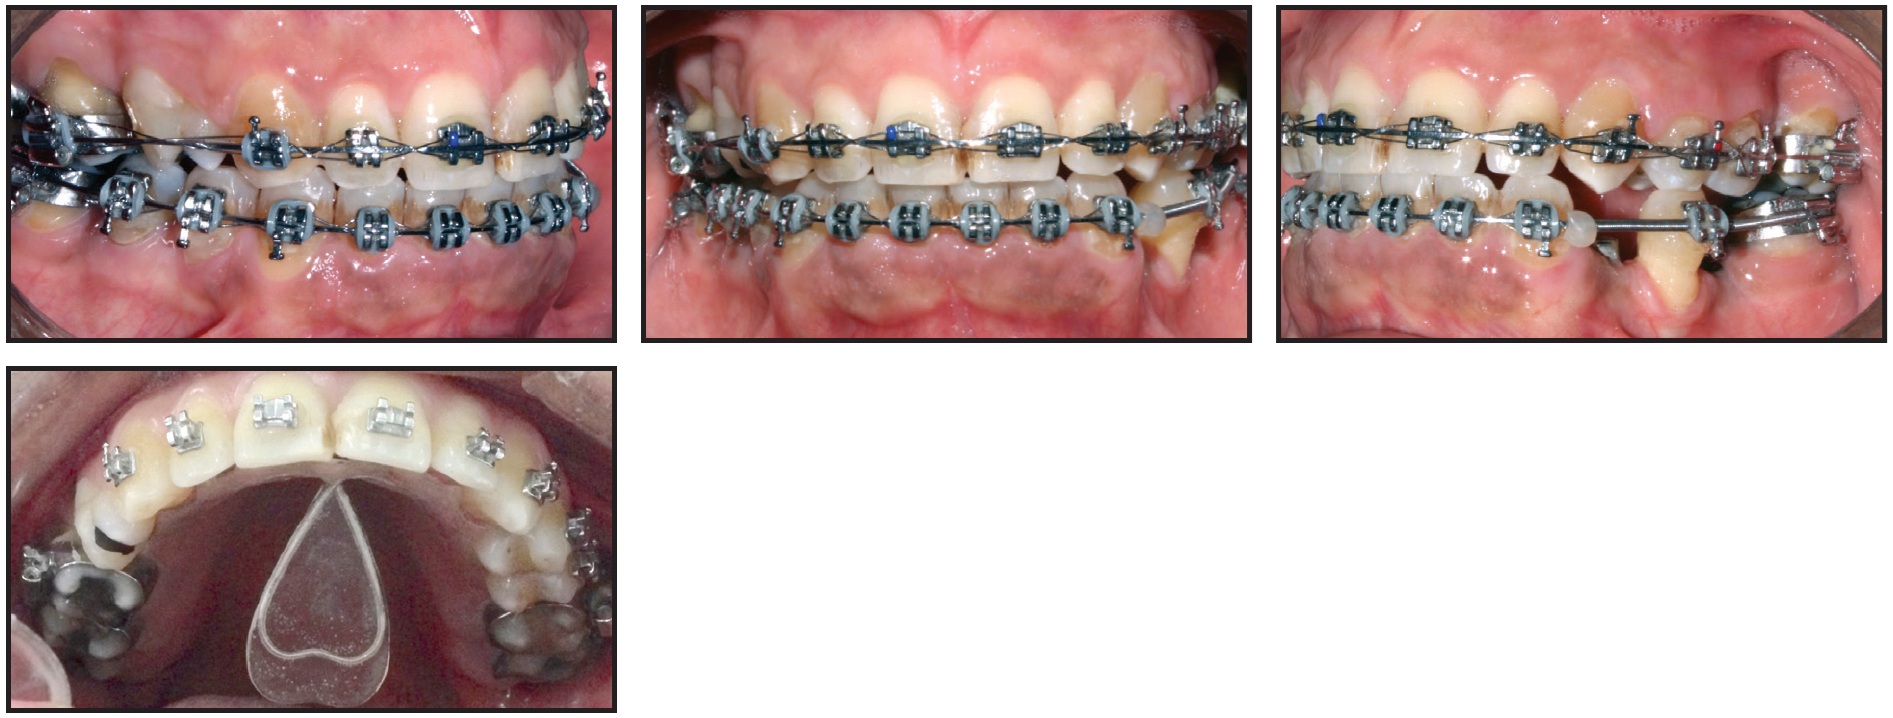

Stainless steel MBT**-prescription brackets*** were bonded in both arches. The initial archwires were .014" nickel titanium, progressing to .016" nickel titanium and .018" stainless steel. After 12 months of treatment, the alignment had improved enough to start treatment with the Tongue Rehabilitator.

Rectangular .019" × .025" stainless steel archwires were inserted to improve the occlusion over the next 12 months. During this stage, implants were placed in the edentulous sites of the lower left first premolar and first molar (Fig. 5).

Fig. 5 After 20 months of treatment, including eight months with Tongue Rehabilitator.

Another six months later, after installation of the prosthetic crowns, the fixed appliances were removed.

A lingual 3-3 retainer was bonded in the lower arch, and a Hawley-type retainer was delivered for the upper arch. At bedtime, the Tongue Rehabilitator could be inserted into the telescopic tube of the retainer’s acrylic palatal plate. This approach fit well with the patient’s routine, since he worked with the public and his speech was affected when he was wearing the device.

Total orthodontic treatment time was 30 months (Fig. 6). At the three-month follow-up visit, we made slight adjustments to the retainer and Tongue Rehabilitator. The patient reported that his sleep quality had improved and he was waking up more refreshed, and that his wife also slept more comfortably.